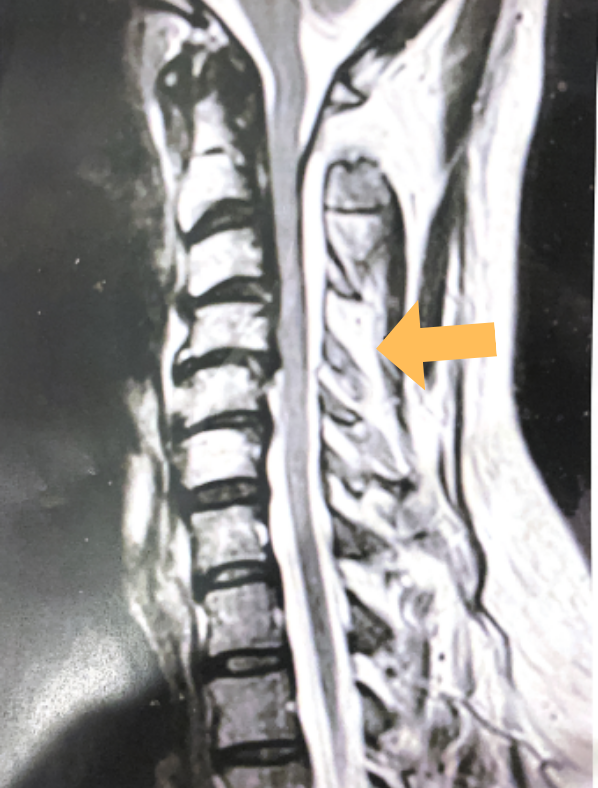

This 57 year-old male presents with severe neck, left shoulder and arm pain and weakness in his hand since being involved in a motor vehicle accident nine months prior. The patient had subsequent left shoulder surgery although he still complained of pain postoperatively and his weakness persisted. He was on no blood thinners. He underwent imaging. The cervical spine MRI revealed an extensive dorsal epidural collection from C1-2 through C5 with associated spinal cord compression. In addition there were multisegmental degenerative changes with foraminal stenosis worse at C4-5 (Fig. 1a and 1b).

(1a) Sagittal and axial T2-weighted cervical MRI demonstrating extensive dorsal epidural collection with hyperintense signal consistent with fluid causing spinal cord compression.

(1b) Hyperintense signal (arrow) at the C3-4 interspinous space consistent with ruptured interspinous ligament,C4-5 (Fig. 1a and 1b).

The fluid was possibly consistent with CSF versus chronic hematoma. The patient was also noted to have a high signal within the interspinous space of C3-C4. This high signal was consistent with a ruptured C3-4 interspinous ligament. Cervical flexion-extension x-rays demonstrated 6 mm of widening of the C3-4 interspinous space on flexion x-ray consistent with cervical instability (Fig. 2a and 2b).

It was felt that the patient was unstable and the patient had signs of early cervical myelopathy secondary to spinal cord compression. The patient consented to undergo exploration and evacuation of the collection and to decompress and stabilize the cervical spine. Upon laminectomy we noticed a ruptured C3-4 interspinous ligament that was consistent with the preoperative imaging studies. After revealing the epidural space during the laminectomy, a large dorsal membrane or pseudomeningocele was noted above a clear fluid collection that was posterior to the dura that was compressing the spinal cord. This membrane was fenestrated and we evacuated the collection which was consistent with CSF. Also during the course of the laminectomy we noted that the source of the CSF leak to be on the left at the takeoff of the C4 nerve root for which the dural sleeve was “degloved” but the fascicles were intact. We repaired with muscle and dural sealants. We completed a C2-C7 laminectomy. The patient had an additional fusion C3-C6 with segmental instrumentation to prevent kyphotic deformity.